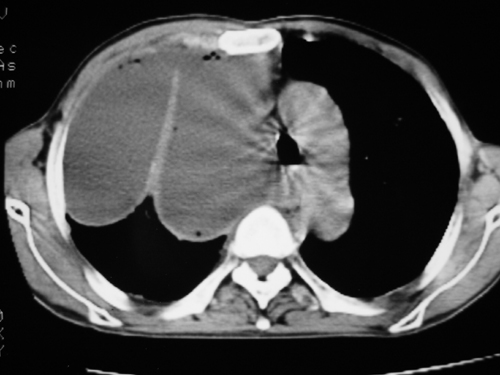

以下是引用yangyudong333在2008-4-29 5:46:00的发言:[br]1左上叶结节呈分叶状,边缘毛刺,考虑肺癌并纵隔淋巴结转移可能性大,结核待排,[br] [br]2右侧多发包裹性胸腔积液